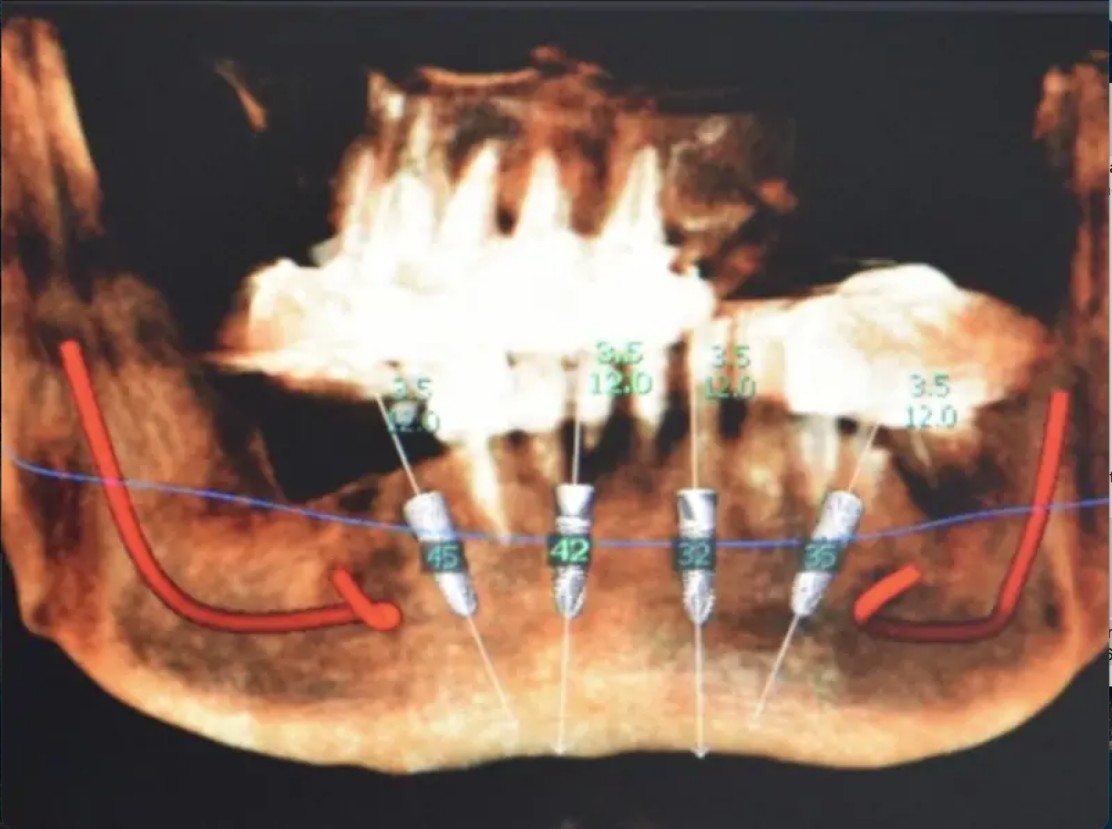

Во время хирургического сеанса подготовка лож под имплантаты проводилась с помощью направляющей дуги, которую необходимо установить в медиальной области и которая дает представление о правильном позиционировании имплантатов при концепции «все на четырех» или «все на шести».

Шаблон позволяет легко определить наклон препарирующих инструментов, а также выбрать угловой монокулярный альвеолярный протез (MUA). Во время второго сеанса мы просто установили абатменты Multi unit и зафиксировали балку протеза соответствующими винтами, прежде чем примерить и проверить окклюзию постоянного протеза.